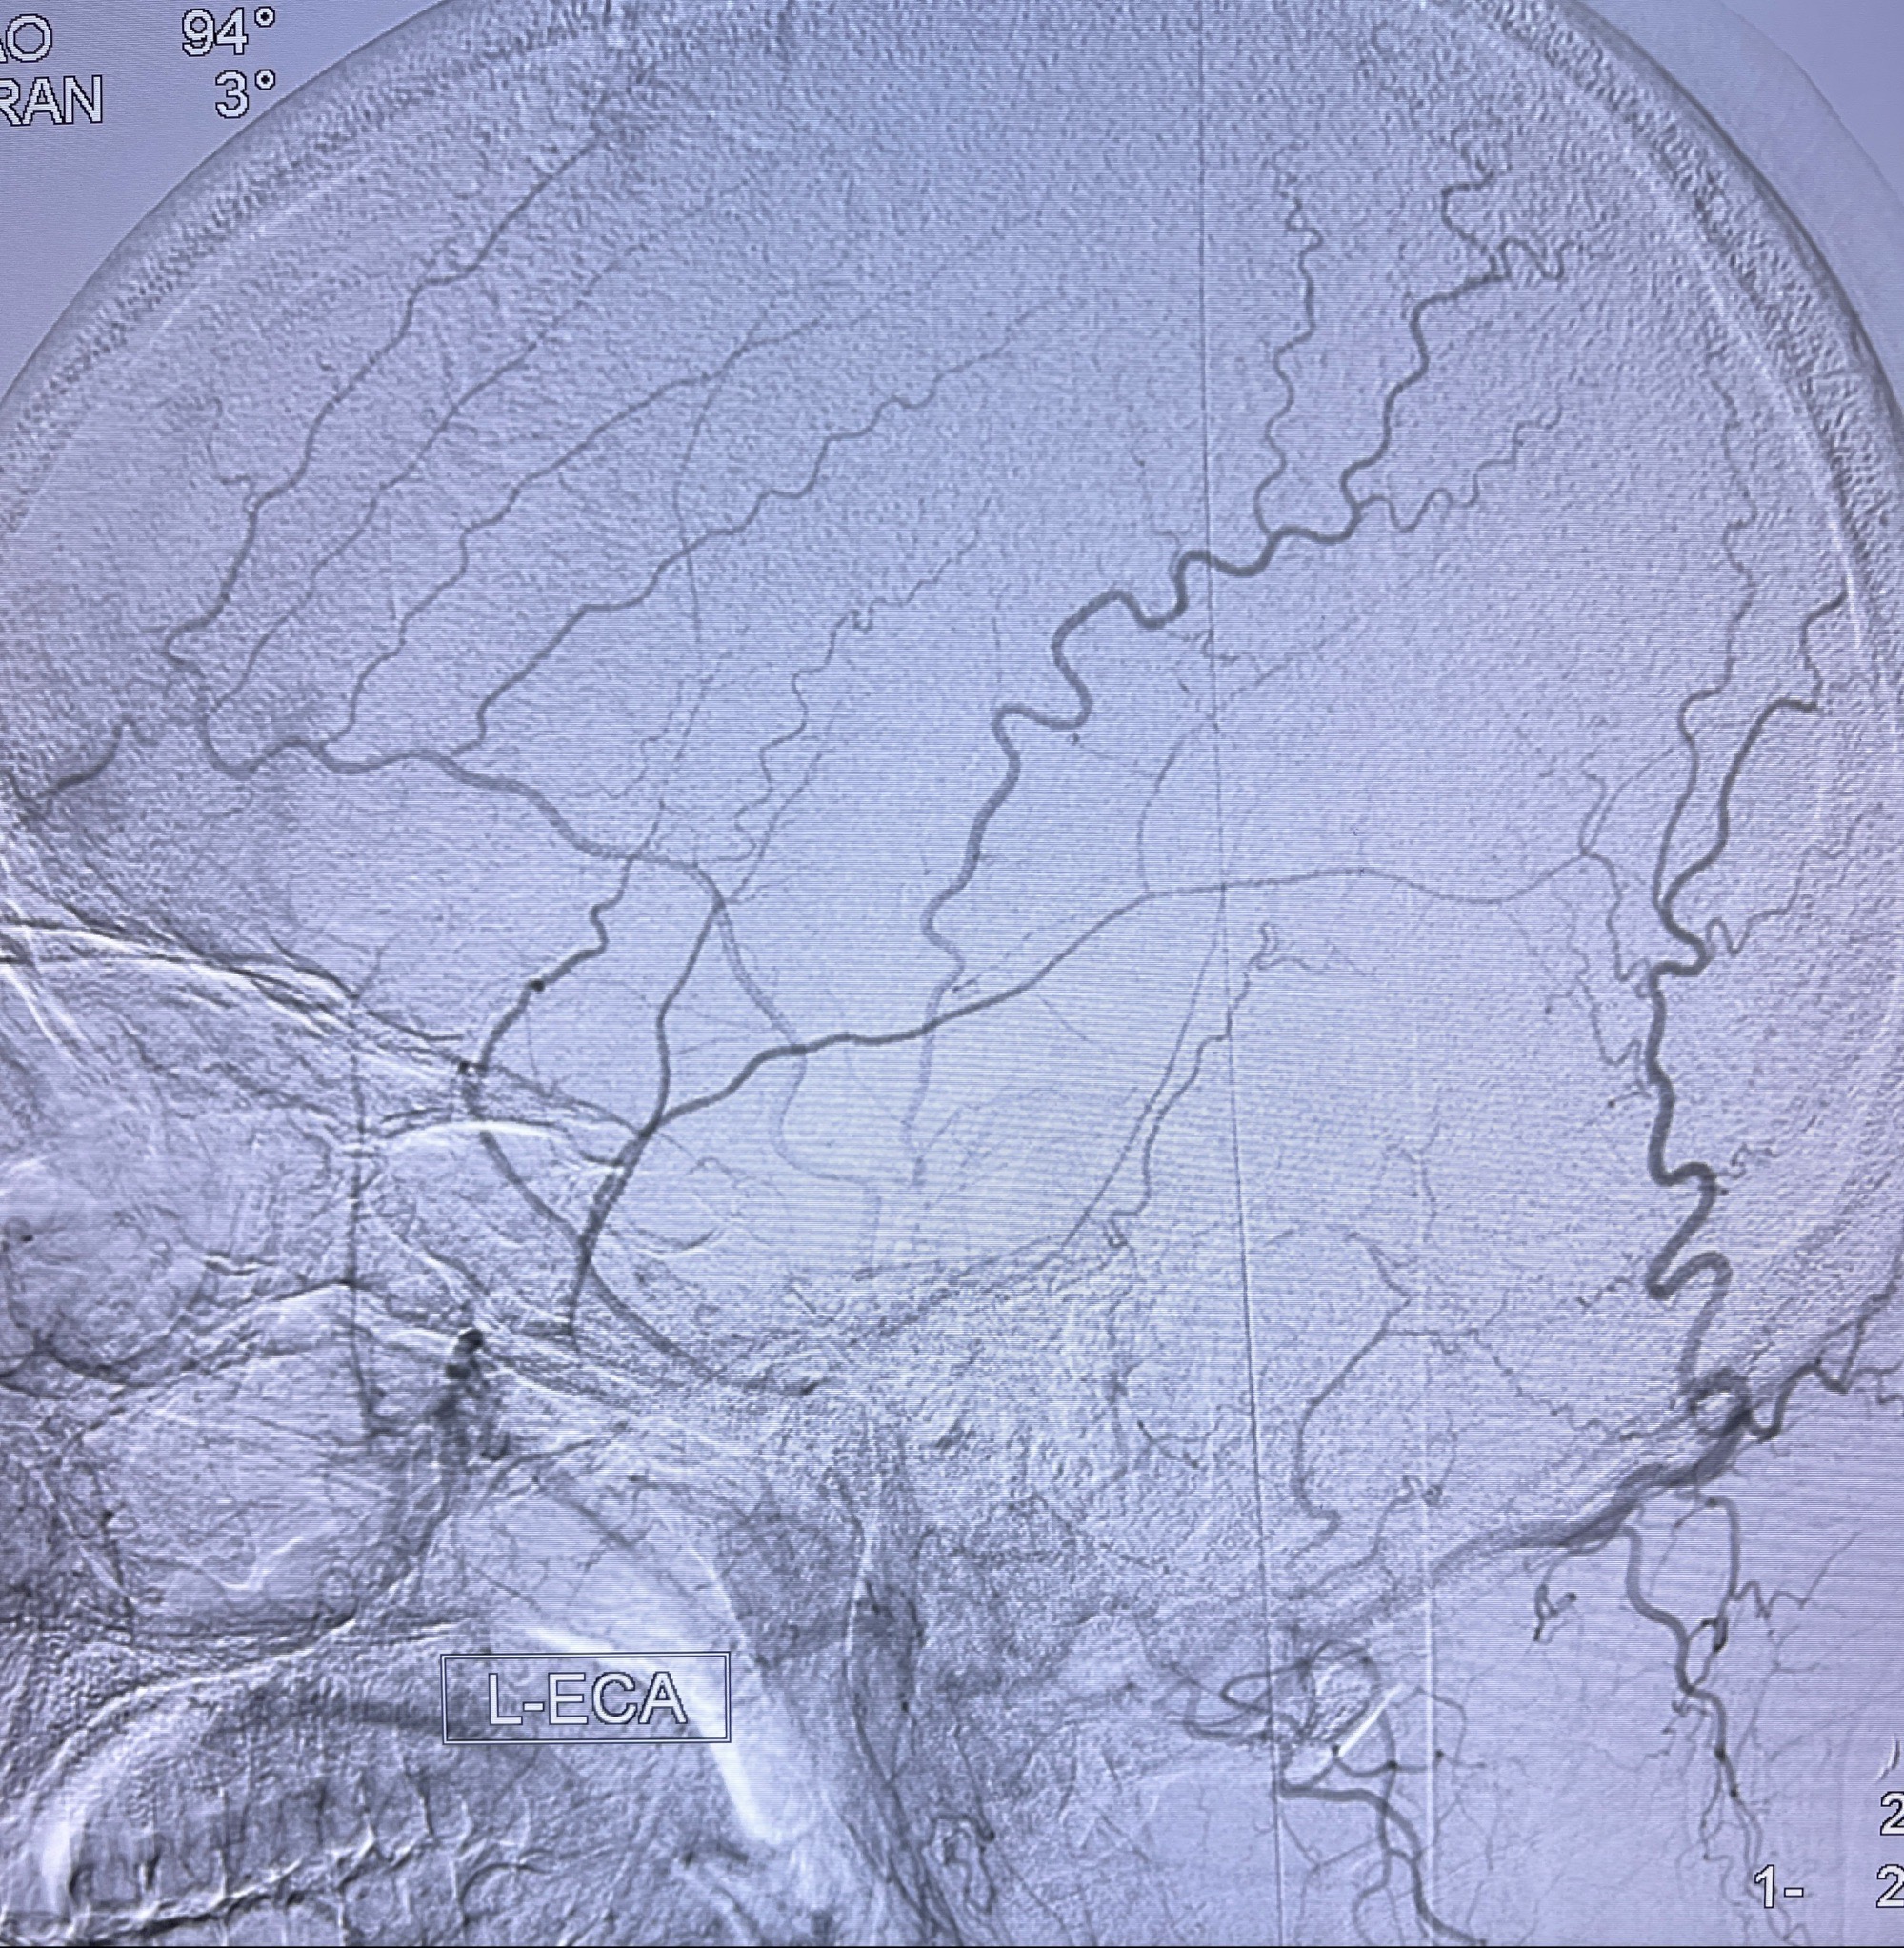

2023年8月21日]景德镇市第一人民医院脑血管造影检查,提示:主动脉弓、双侧颈总动脉、锁骨下动脉造影未见异常,左侧大脑前动脉静脉瘘。

2023-09-13全脑血管造影:前颅底硬脑膜动静脉瘘,供血动脉为双侧胼周动脉、眼动脉脑膜支,静脉向上矢状窦方向引流